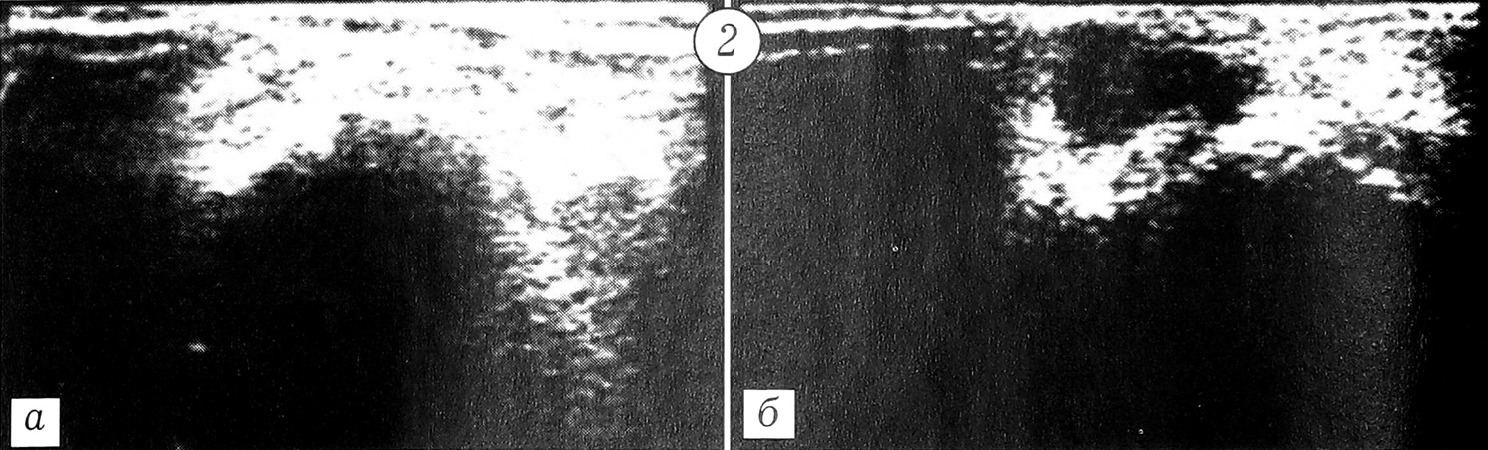

В исследуемую группу вошли 12 больных с повреждениями голеностопного сустава в возрасте от 25 до 45 лет. Давность травмы составляла от 30 мин до 3 ч. Аддукционно-супинационный механизм травмы имел место у 2 пациентов, аддукционнопронационный — у 10. Рентгенологически у 6 больных повреждений костей, образующих голеностопный сустав, не выявлено, у остальных диагностированы отрывы пластинок кортикального слоя по наружной поверхности тела таранной кости. На представленной рентгенограмме одной из больных (рис. 1) видна нечеткость контуров верхушек наружной и внутренней лодыжек и заднего края большеберцовой кости, ширина свободного межберцового пространства составляет 8 мм, наслоение берцовых костей 7 мм; отсутствие костных фрагментов свидетельствует о неполном отрыве связок.

Рис 1. Рентгенограмма правого голеностопного сустава больной С. 29 лет. Диагноз: повреждение передней малоберцово-таранной связки, отрыв кортикальной пластинки от наружного края тела таранной кости.